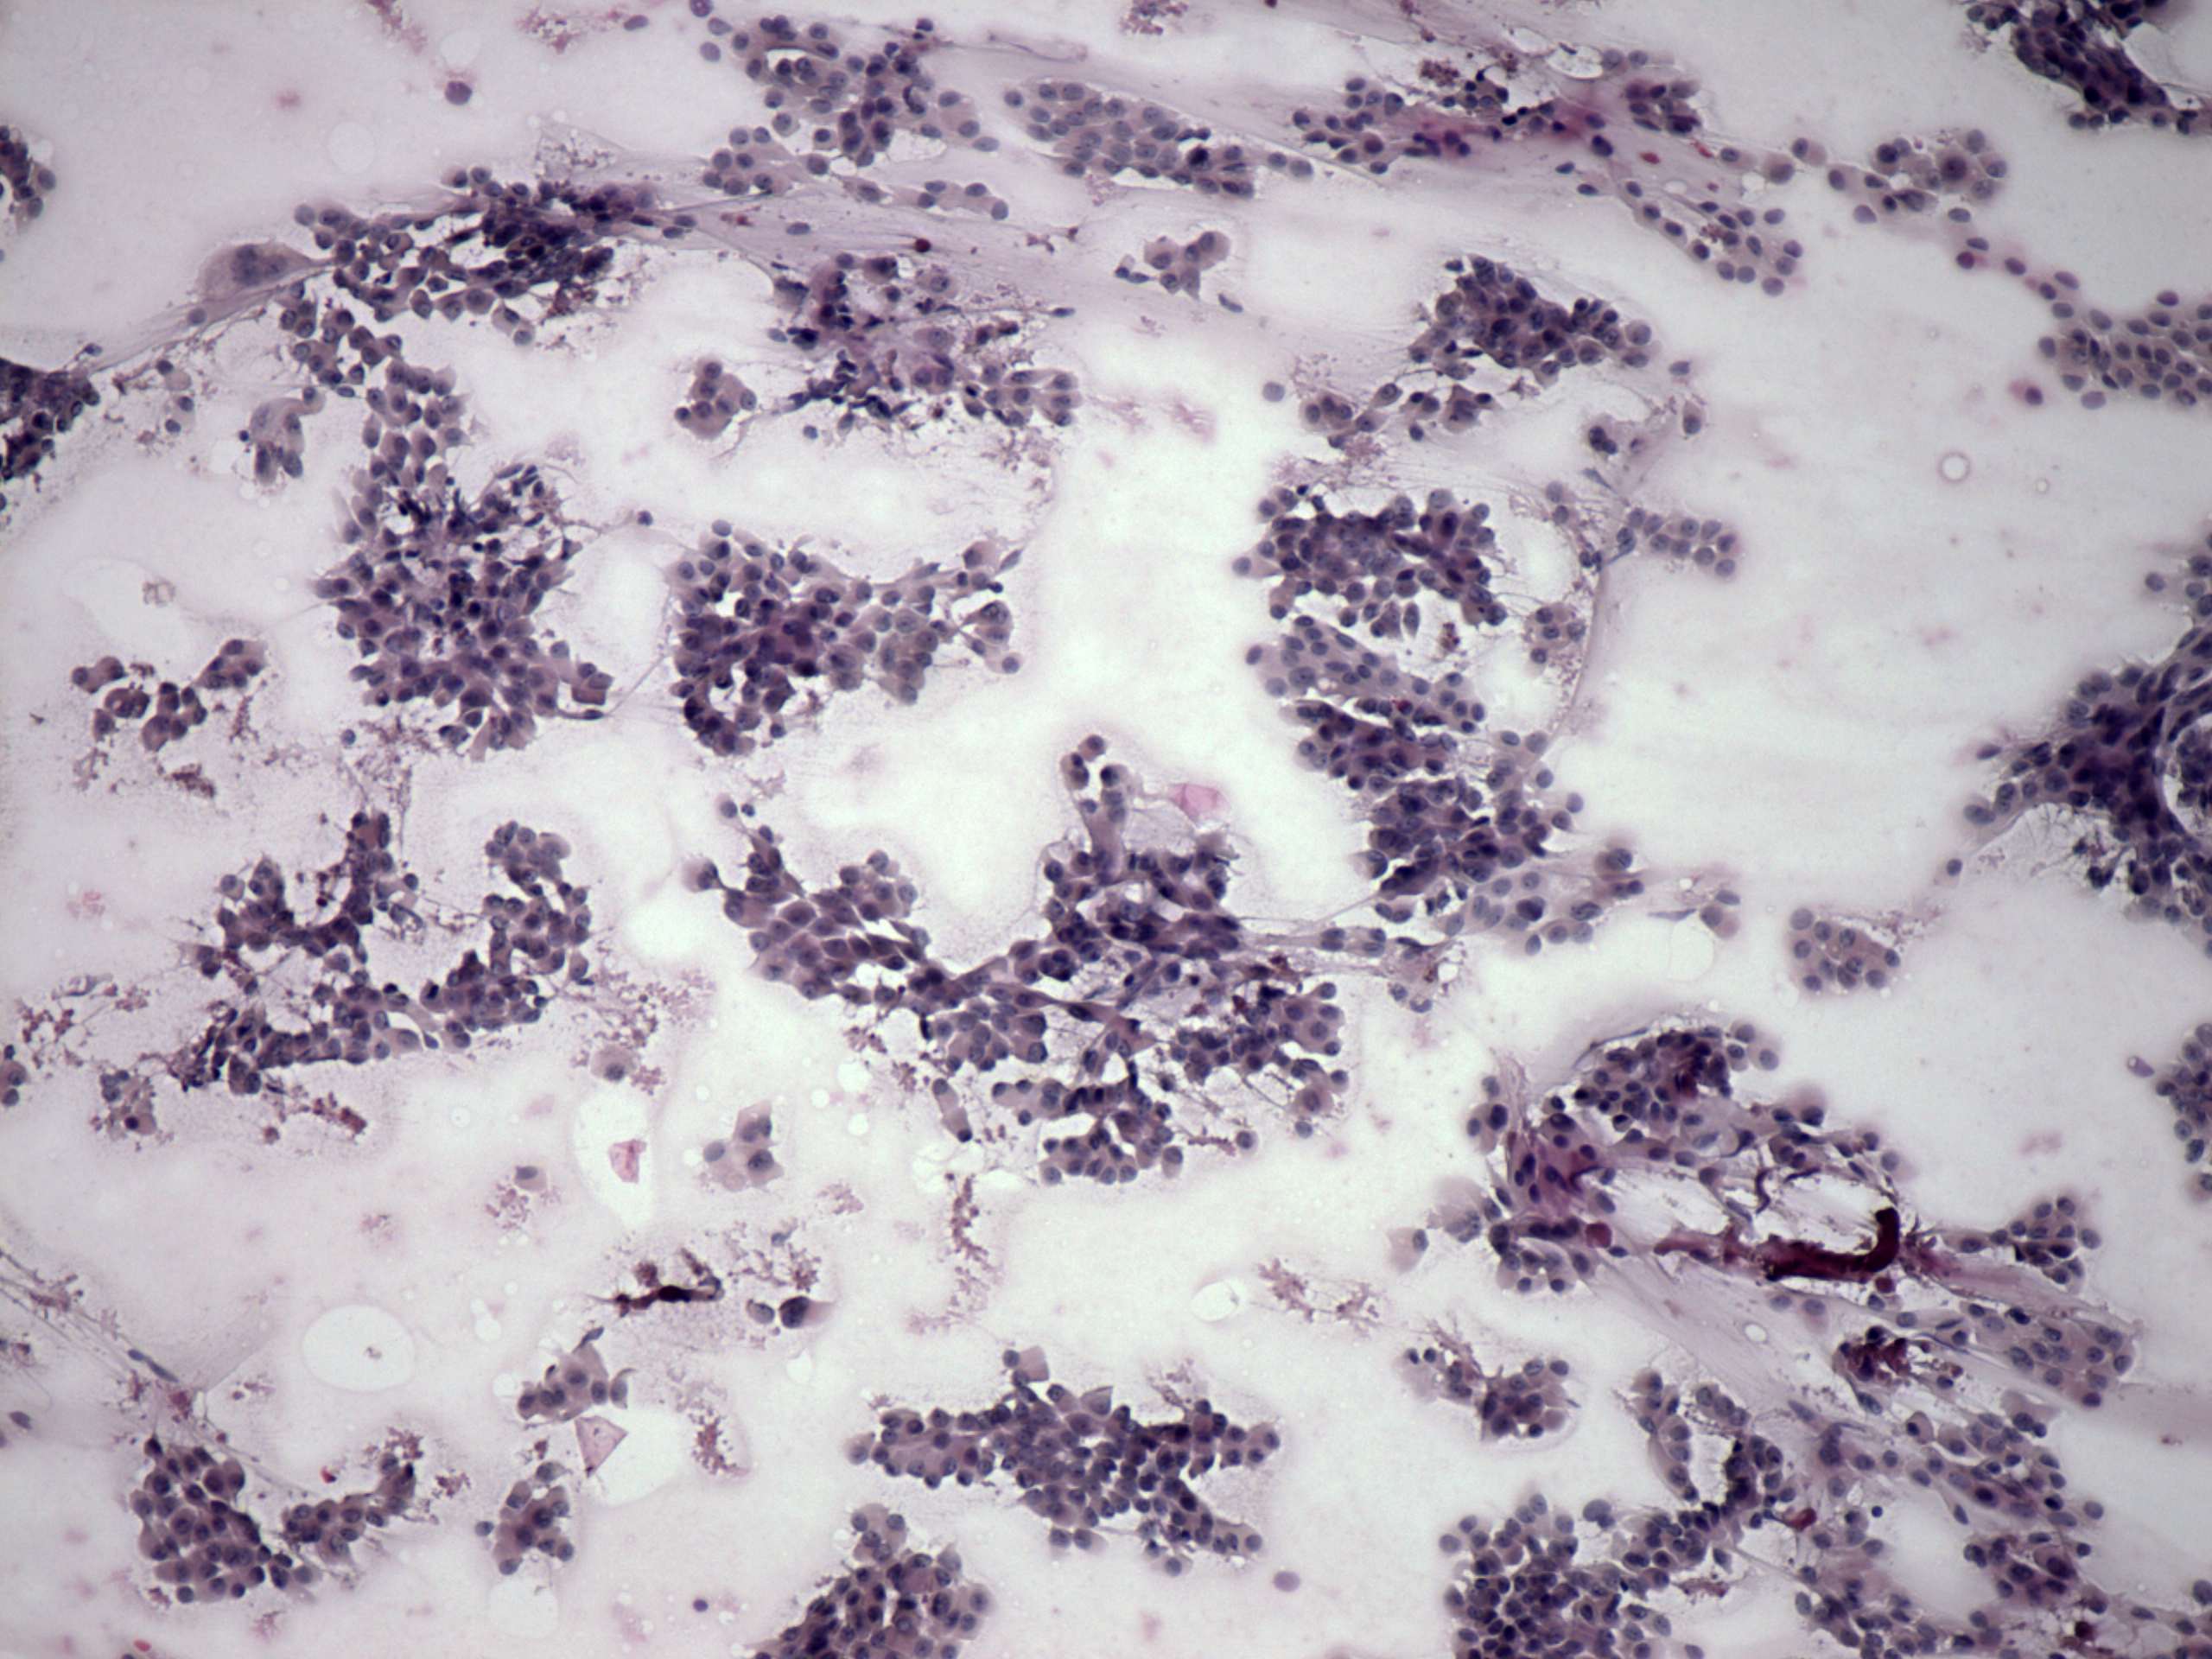

Pap-smear, 100x.  Loose clusters of follicular cells are demonstrated.